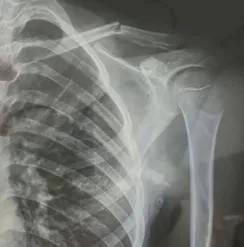

10月30日,内蒙古自治区赤峰市宁城县苏木皋小学一学生家长贾女士给记者打来电话,介绍了孩子被打的原因花都贵金属回收店。贾女士称,放学通道的墙上有一个电灯的开关,好多孩子放学时都随手去拨弄开关。出于安全考虑,学校和老师都禁止孩子拨弄开关。23日放学时,他儿子和另一个同学调皮,再去拨弄了那个开关,被正在值班的另一个班的班主任发现,把她儿子打了,且打骨折了。

图片由报料者提供